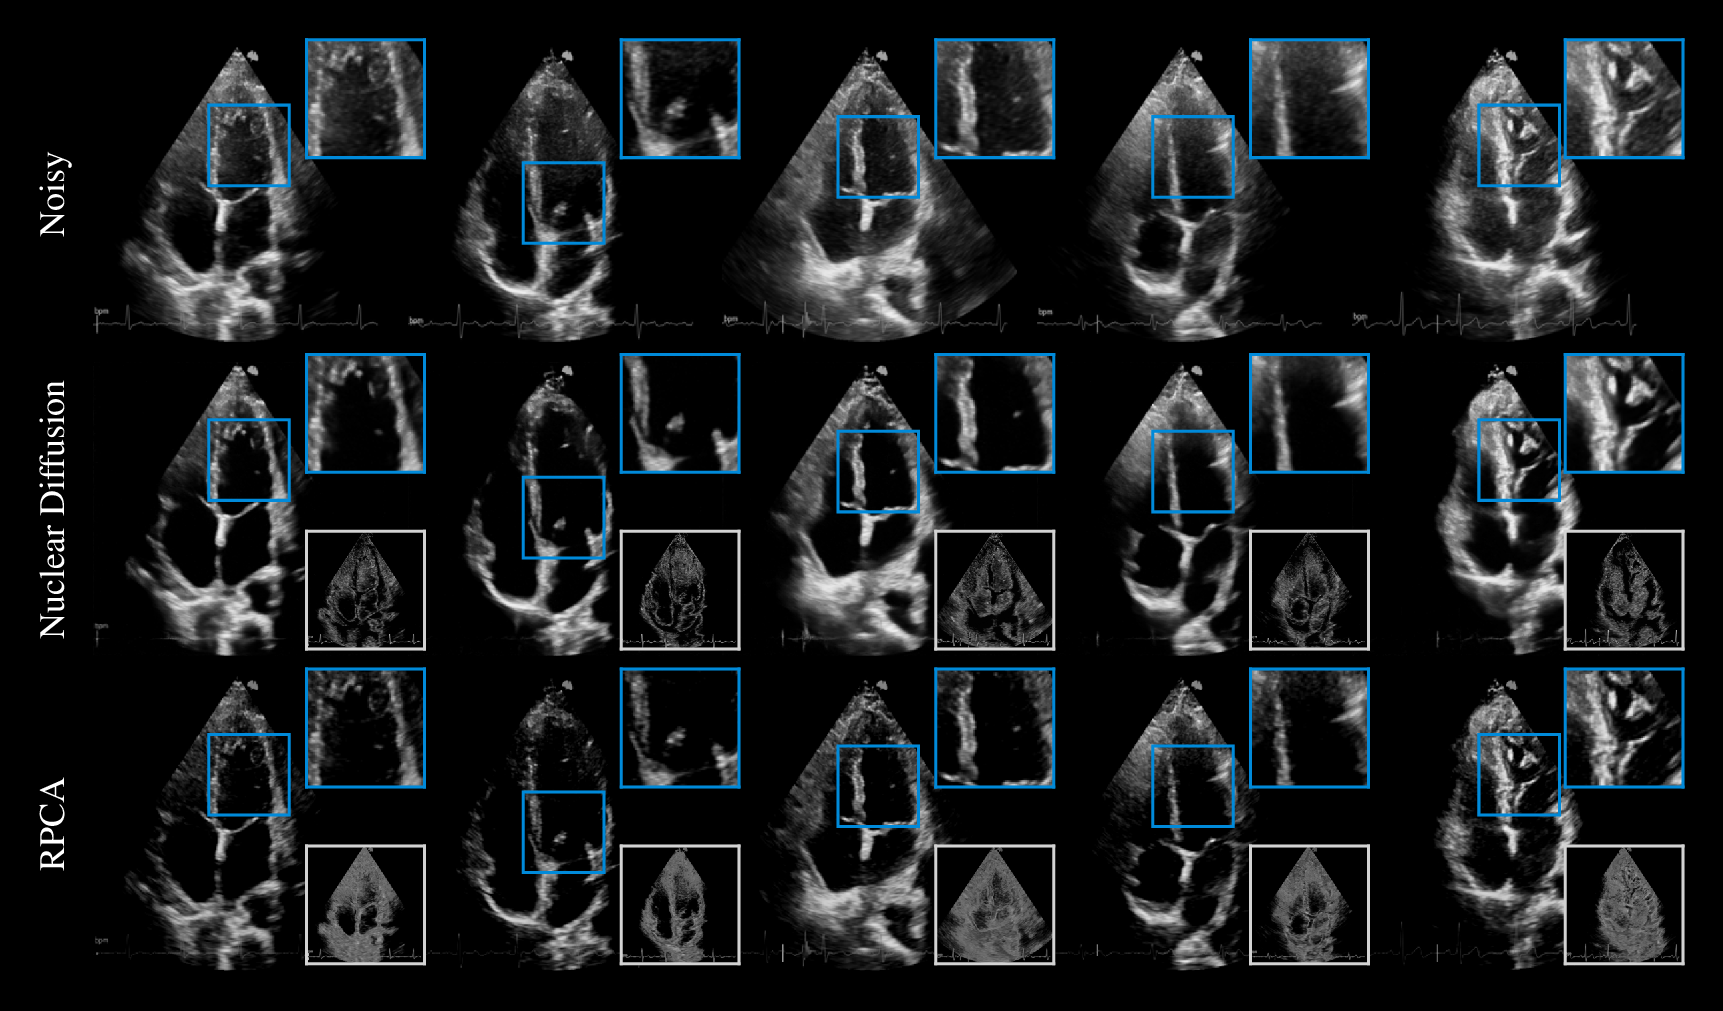

Qualitative comparison on cardiac ultrasound dehazing. While both methods suppress haze (shown in the insets), RPCA tends to excessively attenuate tissue, resulting in sparse structures, whereas Nuclear Diffusion better preserves anatomical detail.